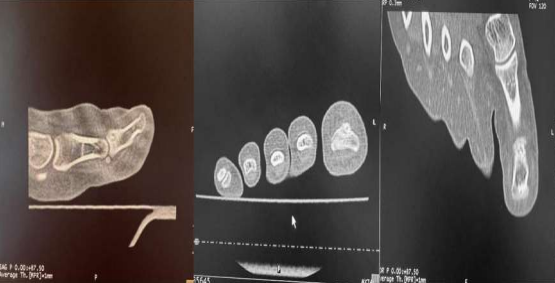

Figure 3: A CT scan showed the nidus surrounded by sclerosis.

CT is the technique of choice, with a sensitivity of 96-100% (3), and enables us to visualize the tumor in its pathognomonic form.

Figure 3